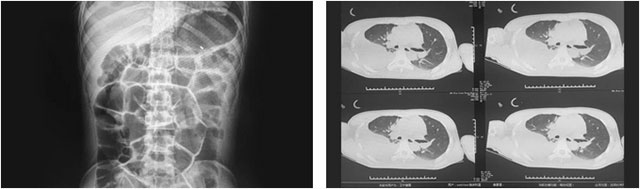

在該院經(jīng)過(guò)半個(gè)多月的對(duì)癥支持治療后,小耿卻仍然昏迷不醒。隨著病情進(jìn)一步惡化,小耿又被查出兩肺挫傷,左側(cè)氣胸,兩側(cè)胸腔積液伴有肺膨脹不全,右側(cè)胸腔積血,且伴有腸梗阻等病癥,病情非常嚴(yán)重。隨后,醫(yī)院又對(duì)其進(jìn)行胸腔閉式引流,予以禁食、胃腸減壓等對(duì)癥治療,但仍無(wú)明顯起色。

“腦干損傷、創(chuàng)傷性硬腦膜下積液、創(chuàng)傷性蛛網(wǎng)膜下出血、肺挫傷、肺部感染、創(chuàng)傷性氣胸、創(chuàng)傷性血胸、創(chuàng)傷性胸腔積液、腸梗阻、低蛋白血癥……”,潘仁龍主任介紹,患者剛來(lái)院時(shí)病情非常嚴(yán)重,其因外傷起病,多發(fā)損傷,其中最嚴(yán)重的是腸梗阻、右肺血?dú)庑丶胺尾繅嚎s嚴(yán)重,當(dāng)時(shí)其胸腔血性積液非常嚴(yán)重,一天引流量約為170毫升,需及時(shí)治療和控制。

▲ 來(lái)院時(shí)查體顯示:多發(fā)損傷嚴(yán)重,腸梗阻、兩肺挫傷及右肺血?dú)庑?/font>

同時(shí),潘主任表示,小耿意識(shí)障礙嚴(yán)重,經(jīng)過(guò)格拉斯哥昏迷評(píng)分法(GCS)評(píng)估,其得分僅為4分,屬重度昏迷,不能言語(yǔ),查體也無(wú)法配合,身上當(dāng)時(shí)還插滿了各種治療管,如胃管、尿管、塑料氣切套管及右側(cè)胸腔閉式引流管等。